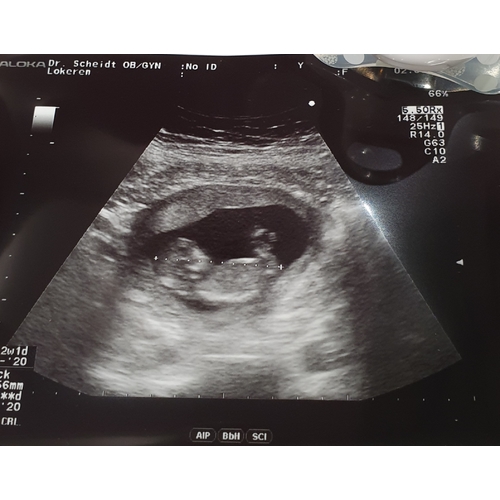

13+4 .. kan iemand het zien? 😂

Jij kunt al wen geslachtsecho laten doen... die heb ik ook staan op 13 weken... hoef je niet te gissen naar de nub....